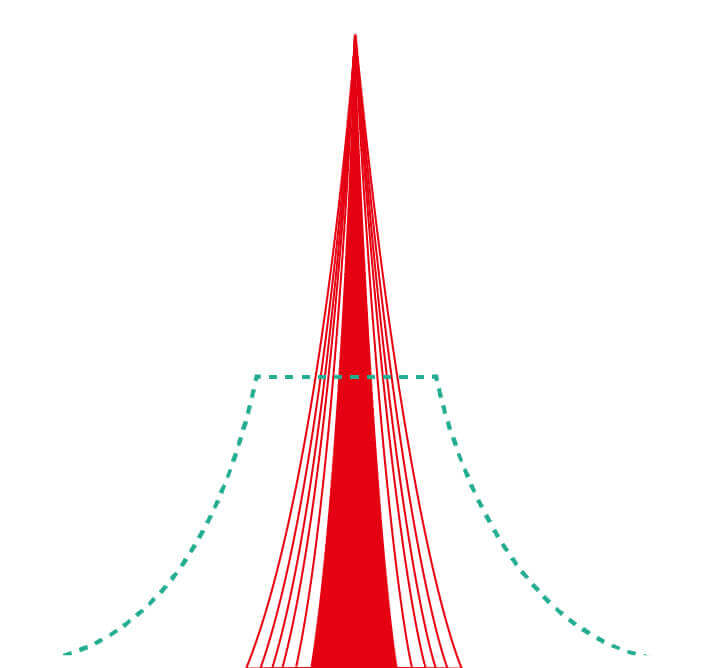

(Versatile Intelligent Staining Technology)

能够凸显黏膜浅层血管轮廓和黏膜表面微结构,适用于中、近景观察下的早癌精确诊断。